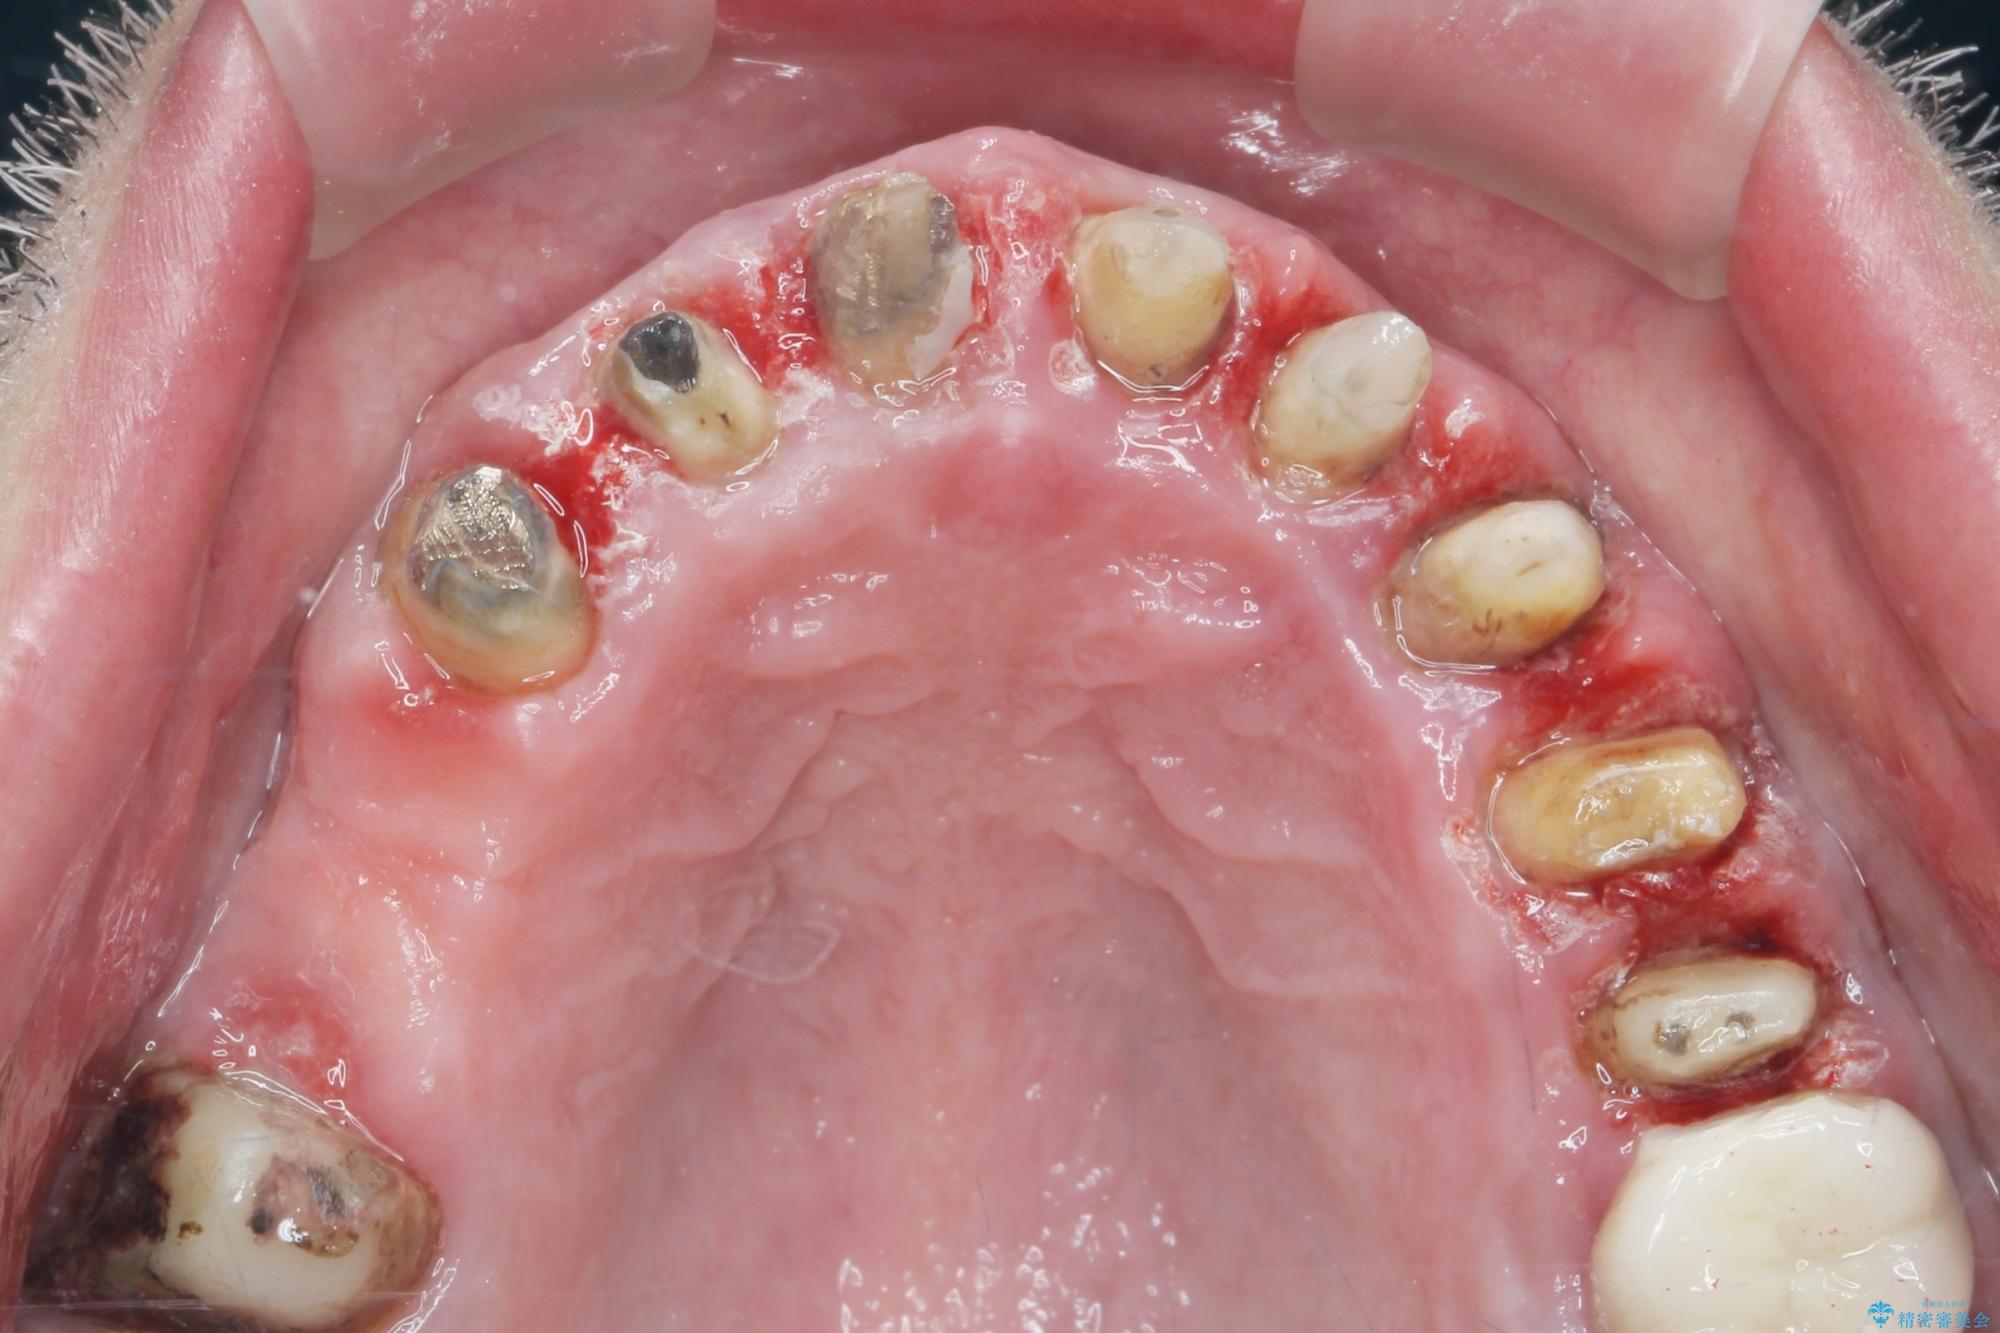

[ 歯周外科手術 ] セラミック治療後の歯ぐきの違和感

歯周組織検査を行うと歯ぐきからは容易に出血し、X線検査より歯とセラミッククラウンの適合が悪い(ピッタリと合っていない)状態が示唆され、歯ぐきの炎症を惹起している状態でした。

セラミッククラウンを除去し仮歯を装着し、歯周外科手術を行い歯ぐきの状態を改善したのち、適合の良いセラミッククラウンを再作製をする治療計画としました。

- 90.2万円(ジルコニアクラウン×6・仮歯×6 ・歯周外科手術)費用は治療当時の料金となります